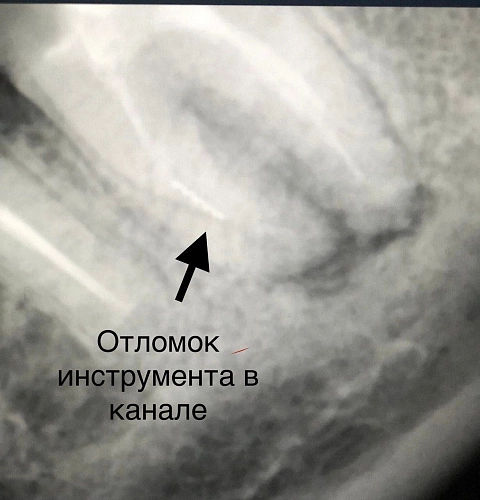

На диагностическом рентгеновском снимке был обнаружен очаг деструкции костной ткани в области данного зуба, так же не полностью запломбированные каналы и отломок инструмента в одном из корневых каналов.

Для того чтобы купировать боль и вылечить зуб необходимо было извлечь отломок, перелечить все корневые каналы и запломбировать их новым пломбировочным материалом. Доктор успешно провел процедуру и таким образом спас зуб от удаления